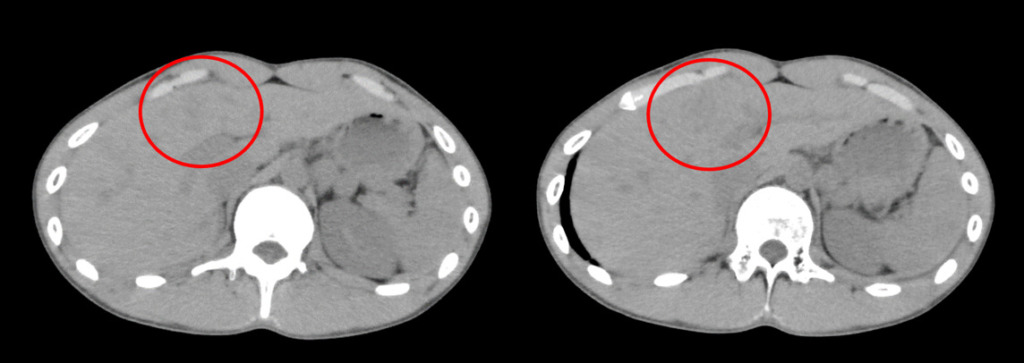

しかし、血液検査の結果で肝酵素の上昇を認め、改めて画像を詳細に確認したところ、肝臓のS4領域にわずかな低吸収域(周囲より黒い部分・↓赤丸部分)が認められました。

こちらは造影CTの所見です。

受診から1時間後に実施された造影CTにより、肝S4に不整形の造影されない領域(血腫)が確認され、肝損傷と診断されました。